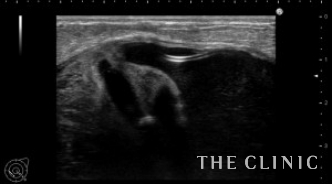

エコー所見です。

右はバッグの破損はありません。左はカプセル拘縮が強くエコーではカプセルとバッグの間に通常見られない組織を認めました。